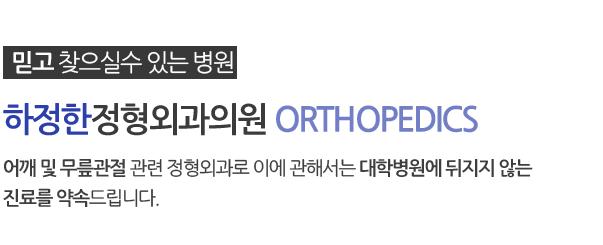

어깨 골절